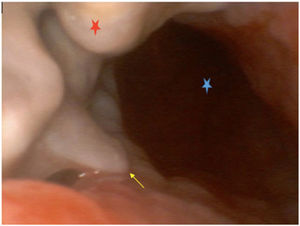

This is the case of a 26-year-old man with upper airway obstruction due to the presence of left anterior cervical mass caused by a diffuse large B-cell lymphoma. Chemotherapy and radiotherapy are started. However, due to the patient’s poor clinical course, a tracheostomy is performed. A new episode of airway obstruction occurs one week later as seen on the video-bronchoscopy (Fig. 1) with tracheal lumen infiltration (blue asterisk) due to mediastinal mass (red asterisk), prolapsed tracheal cartilage (yellow arrow), and a 5 cm fistula on the left wall. Both the distal trachea and the main carina appear normal. The CT scan performed (Fig. 2A) reveals the presence of a destructured trachea (yellow arrow) as in the 3D reconstruction (Fig. 2B).